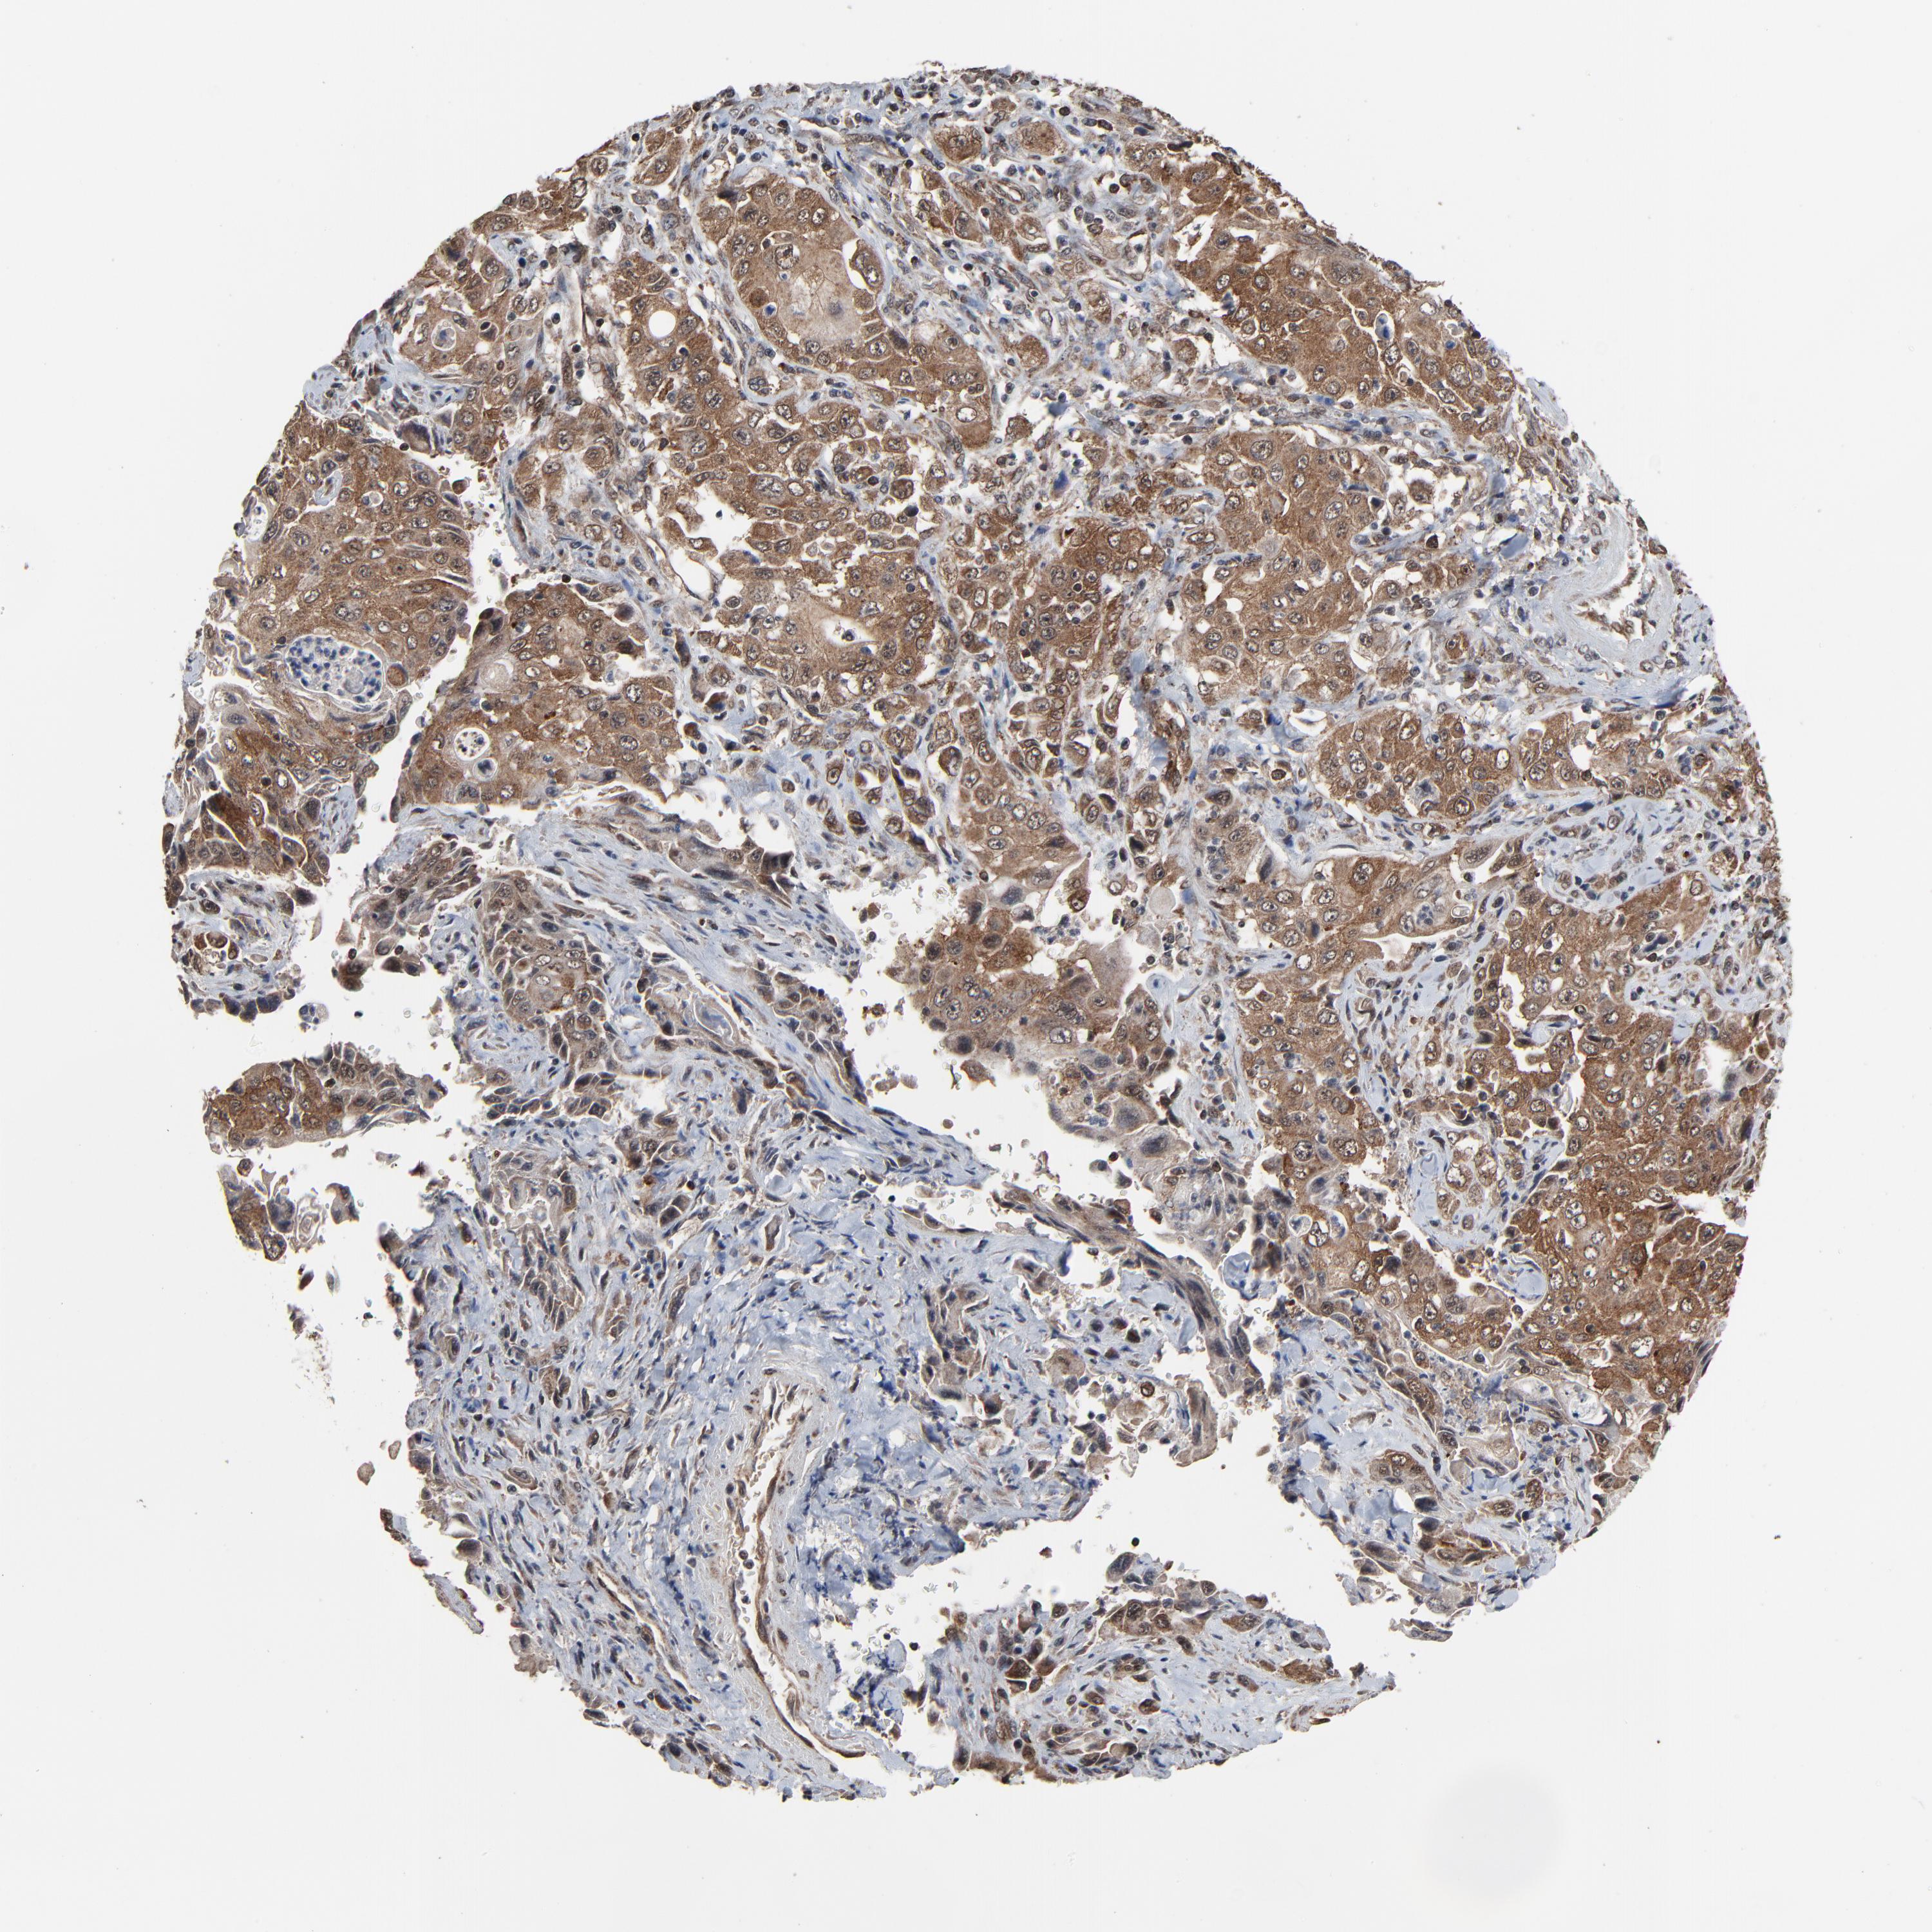

PANCREATIC CANCER - Protein expressioni

A mouse-over function shows sample information and annotation data. Click on an image to view it in a full screen mode. Samples can be filtered based on level of antibody staining by selecting one or several of the following categories: high, medium, low and not detected. The assay and annotation is described here.

Note that samples used for immunohistochemistry by the Human Protein Atlas do not correspond to samples in the TCGA dataset.

Antibody stainingi

Antibody staining in the annotated cell types in the current human tissue is reported as not detected, low, medium, or high, based on conventional immunohistochemistry profiling in selected tissues. This score is based on the combination of the staining intensity and fraction of stained cells.

Each image is clickable and will lead to virtual microscopy that enables deeper exploration of all samples and also displays staining intensity scores, fraction scores and subcellular localization as well as patient and tissue information for each sample.

Antibody HPA003050

Staining

High

Medium

Low

Not detected

Intensity

Strong

Moderate

Weak

Negative

Quantity

>75%

75%-25%

<25%

None

Location

Nuclear

Cytoplasmic/membranous

Cytoplasmic/membranous,nuclear

Adenocarcinoma, NOS